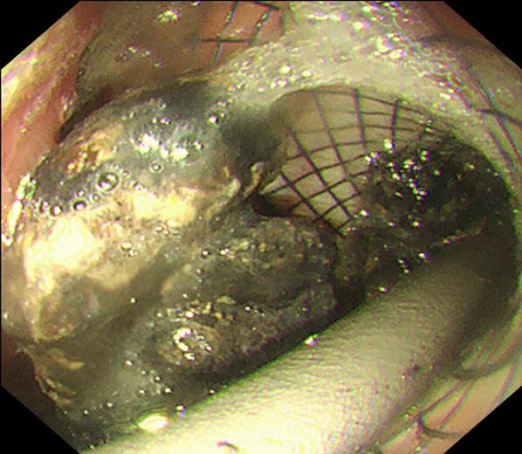

导丝、切开一气呵成,通道建立。一枚胰腺WON专用引流支架(LAMS)被成功置入,即刻可见大量液体流出至胃腔内。但李阿姨的坏死腔巨大,内容物黏稠。如果只用单支架,一旦堵塞或移位,效果将大打折扣。

为确保引流充分持久,孙家琛创新性地在LAMS支架内,再叠加置入一枚“双猪尾”塑料支架,构建了一个独特的“双保险”引流结构——两个支架互为补充,即使其中一个出现堵塞,另一个仍能维持引流。这一设计,极大提升了长期引流的稳定性与通畅性。

内镜下操作在LAMS支架内,叠加置入“双猪尾”塑料支架,构建独特的“双保险”引流